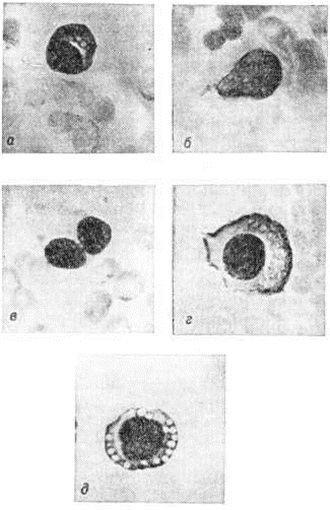

Гистологически в костном мозге при Миеломная болезнь обнаруживают разрастания плазматических клеток разнообразного вида. Гистологически плазматические клетки при Миеломная болезнь чаще всего характеризуются грубым, эксцентрично расположенным ядром и довольно обильной базофильной цитоплазмой; иногда ядро с тонкой структурой хроматина содержит 1—3 нуклеолы, а базофилия цитоплазмы выражена слабо. Существуют различные переходные формы между этими вариантами (рисунок 1); для Миеломная болезнь характерно присутствие гигантских дву и многоядерных плазматических клеток и так паз. пламенеющих клеток, обильная цитоплазма которых имеет неровные контуры и розоватый оттенок по краям. Часто встречаются различные варианты плазматических клеток, содержащих ацидофильные тельца Расселла, количество и расположение которых в цитоплазме определяют вид клеток, обозначаемых как гроздьевидные (grape cells), ягодовидные (morula cells), тезауроциты (клетки накопления) или клетки Мотта. Некоторые авторы наблюдали цитохимически негативные кристаллические включения в цитоплазме миеломных клеток.

Электронная микроскопия плазматических клеток при Миеломная болезнь позволяет выявить гипертрофию протеин-синтезирующих структур — шероховатую эндоплазматическую сеть в виде мешков и цистерн, оттесняющих ядро к периферии, полирибосомы и развитой комплекс Гольджи. Ацидофильные тельца выявляются в виде оптически плотных гранул, содержащих аморфную белковую субстанцию. Полагают, что они состоят из конденсированного парапротеина. В связи с высоким содержанием белка и рибонуклеопротеидов цитоплазма этих клеток резко пиронинофильна, имеет ШИК-положительную реакцию, люминесцирует при окраске тиофлавином Т. Наряду со зрелыми плазмоцитами выявляются плазмобласты, атипичные гигантские одно и многоядерные клетки. Клеточный состав разрастаний варьирует в различных случаях и нередко отличается в разных участках скелета. Разрастания плазматических клеток могут быть узловатыми, диффузными или диффузноузловатыми. Первый вариант, как показывают результаты трепанобиопсии, встречается главным образом в ранние стадии болезни. При этом на фоне нормального костного мозга выявляются множественные, довольно больших размеров (от 200 микрометров и более) очаговые разрастания плазматических клеток (рисунок 2), проникающие в прилежащую ткань. Прогрессирование Миеломная болезнь характеризуется развитием диффузной инфильтрации костного мозга плазматическими клетками (рисунок 3). Нередко это сопровождается развитием обширных узловатых разрастаний (цветной таблица, ст. 33, рисунок 8 и 9). Число клеток нормального гемопоэза заметно снижено. Могут выявляться поля миелофиброза, жировых клеток. Характерно значительное истончение костных пластинок вплоть до полного их исчезновения на больших участках, расширение каналов остеонов (гаверсовых каналов), частичное разрушение коркового вещества с прорастанием плазматических клеток в надкостницу. Рассасывание костной ткани протекает по типу гладкой, пазушной и остеокластической резорбции. Полагают, что остеопороз обусловлен нарушением процессов костеобразования вследствие повышенной секреции в костном мозге фактора, стимулирующего остеокласты. Репаративные процессы резко снижены, однако в ряде случаев наблюдается очаговое образование кости примитивного строения, преимущественно в области микро-переломов и в зонах кровоизлияний по периферии узловатых разрастаний (рисунок 4). Изредка рассасывание костной ткани отсутствует, имеет место утолщение костных пластинок.